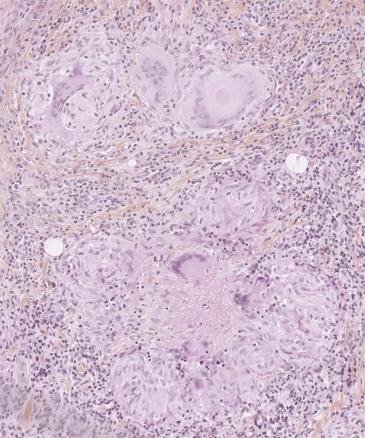

Cet homme de 56 ans vivant avec le VIH et en rupture thérapeutique, était adressé pour une gingivite ulcéro-nécrotique (fig. 1) et des adénopathies sous-mandibulaires bilatérales, évoluant depuis trois semaines. La biopsie a objectivé des granulomes épithélioïdes gigantocellulaires, une nécrose caséeuse (fig 2) et des mycobactéries. L’imagerie thoracique a révélé des nodules pulmonaires évoquant une miliaire tuberculeuse (fig 3).